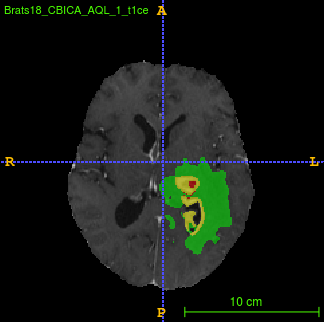

Segmentation of brain tumor from magnetic resonance imaging (MRI) is a vital process to improve diagnosis, treatment planning and to study the difference between subjects with tumor and healthy subjects. In this paper, we exploit a convolutional neural network (CNN) with hypercolumn technique to segment tumor from healthy brain tissue. Hypercolumn is the concatenation of a set of vectors which form by extracting convolutional features from multiple layers. Proposed model integrates batch normalization (BN) approach with hypercolumn. BN layers help to alleviate the internal covariate shift during stochastic gradient descent (SGD) training by zero-mean and unit variance of each mini-batch. Survival Prediction is done by first extracting features(Geometric, Fractal, and Histogram) from the segmented brain tumor data. Then, the number of days of overall survival is predicted by implementing regression on the extracted features using an artificial neural network (ANN). Our model achieves a mean dice score of 89.78%, 82.53% and 76.54% for the whole tumor, tumor core and enhancing tumor respectively in segmentation task and 67.90% in overall survival prediction task with the validation set of BraTS 2018 challenge. It obtains a mean dice accuracy of 87.315%, 77.04% and 70.22% for the whole tumor, tumor core and enhancing tumor respectively in the segmentation task and a 46.80% in overall survival prediction task in the BraTS 2018 test data set.